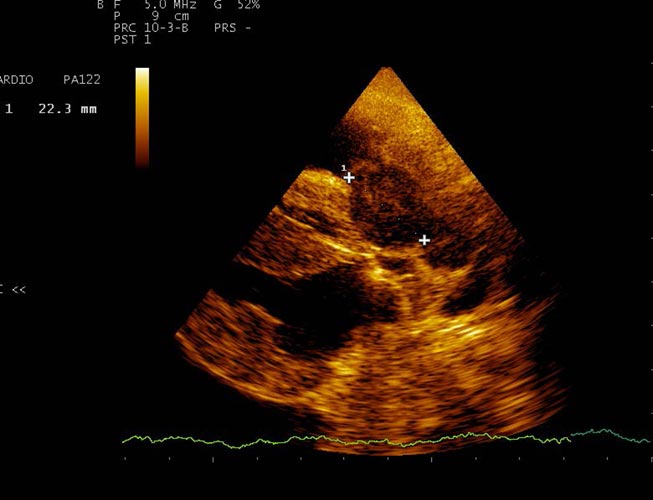

Echocardiographie

Cet examen permet notamment de déterminer l'origine d'un souffle détecté au cours d’une consultation. Il permet aussi d’apprécier les répercussions sur le fonctionnement du cœur.

Selon les résultats de l’examen, un traitement est mis ou non en place. Il diffère en fonction des maladies et des stades d’évolution de celle-ci.